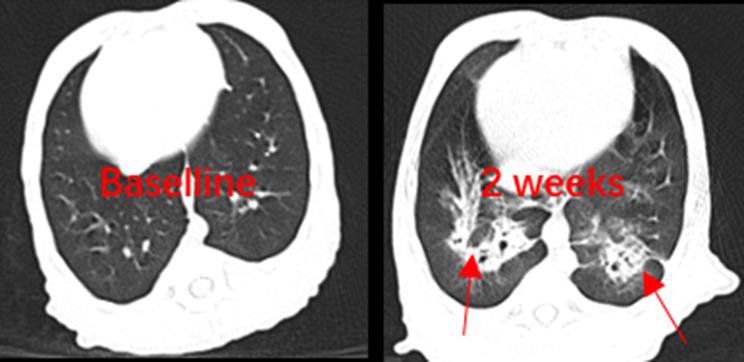

(CT-skener za fibrozu u IPF modelu)

- Fibroza pluća:Naš model replicira kroničnu i progresivnu fibroznu intersticijsku upalu pluća, dopuštajući dubinsko istraživanje ovog složenog stanja.